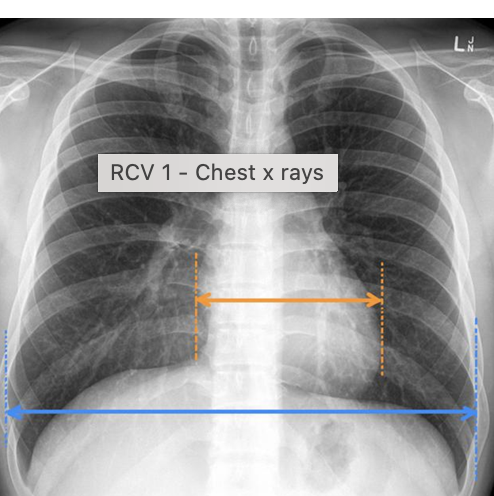

how do you assess for rotation on chest xray?

-the space between the medial clavicle and the margin of the adjacent vertebrae should be equal to each other

-check the ratio of the heart size: width of thorax (normal adult ratio is less than 50%)